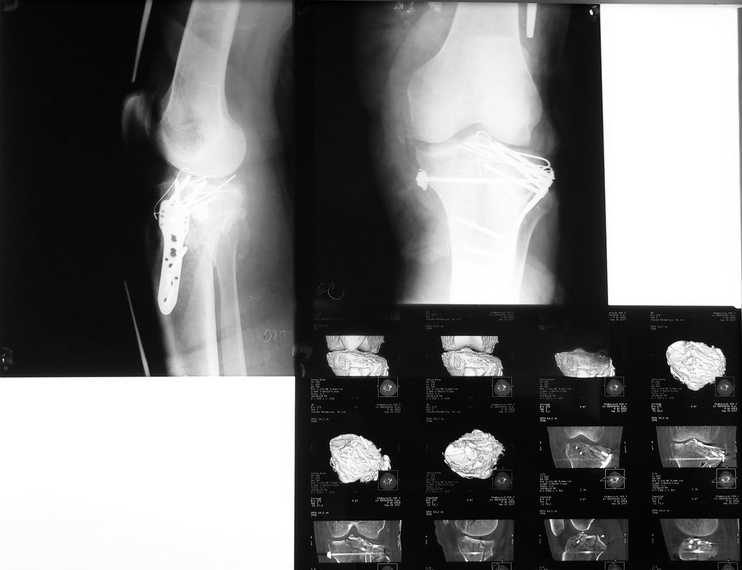

Результат после операции

R-гр контроль и КТ после синтеза межмыщелкового перелома голени. Первичные снимки в сообщении от 20 сентября. Критика коментарии приветствуются. С уважением Пак Л.

Уважаемый Леонид! Интересный, но, в общем-то нередкий случай. Представлен перелом плато большеберцовой кости с импрессией суставной поверхности в зоне наружного мыщелка. Импрессия полностью не устранена, суставная поверхность не поднята до правильного анатомического уровня. Так же мне кажется, что 3,5 мм винты здесь слишком тонки и коротки. В случае восстановления плато понадобилась бы костная или другая пластика дефекта. Пластина, на мой взгляд, желательна более длинная. Однако, и в случаях применения более длинной 4,5 мм пластины с блокированными винтами зачастую для достижения стабильности приходится применять и вторую - как правило 3,5мм реконструктивную пластину по внутренней поверхности. А за случай спасибо! С уважением, Волна